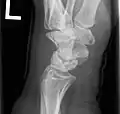

Left hand x-ray with Kienbock's Disease showing 4 mm negative ulnar variance and Kienbock's Disease Stage IIIB

Left hand x-ray with Kienbock's Disease